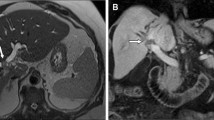

Perihilar cholangiocarcinoma—“Klatskin” tumor—evaluated with 18F-FDG PET/CT and MRI/MRCP. (a) Coronal 18F-FDG-PET/CT shows a hypermetabolic mass in the central liver (white arrow). (b) Coronal MIP MRCP shows dilatation of intrahepatic bile ducts beginning at the confluence of the left and right hepatic ducts secondary to an hilar obstructing mass and no filling of the extrahepatic bile duct (white arrow). (c–e) MRI shows an ill-defined mass in the porta hepatis that shows (c) peripheral arterial phase hyperenhancement (white arrow) and (d, e) slight progressive centripetal enhancement on (d) portal venous and (e) delayed phases (white arrow). 18F-FDG 18F-fluorodeoxyglucose, PET positron emission tomography, CT computed tomography, MRI magnetic resonance imaging, MRCP magnetic resonance cholangiopancreatography, MIP maximum intensity projection

Experience with 18F-FDG PET/CT or PET/MRI in pCCA is much more limited than for iCCA, but it may be helpful in detection of distant metastatic disease (Fig. 2.5).